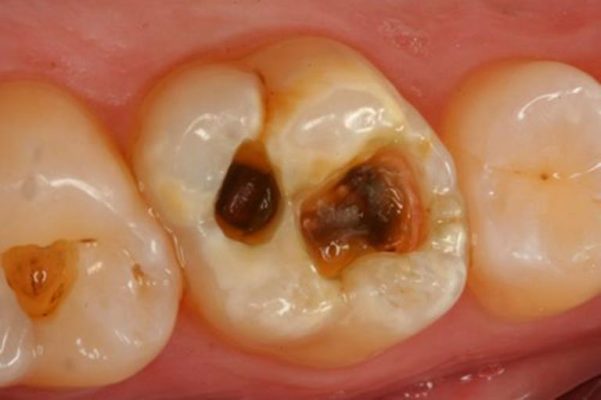

- Untreated Cavities – Deep decay allows bacteria to reach the tooth’s inner structure.

- Cracked or Broken Teeth – Even small cracks can provide a path for bacteria.

Once bacteria reach the pulp, pressure builds inside the tooth — causing pain, inflammation, and sometimes abscess formation.